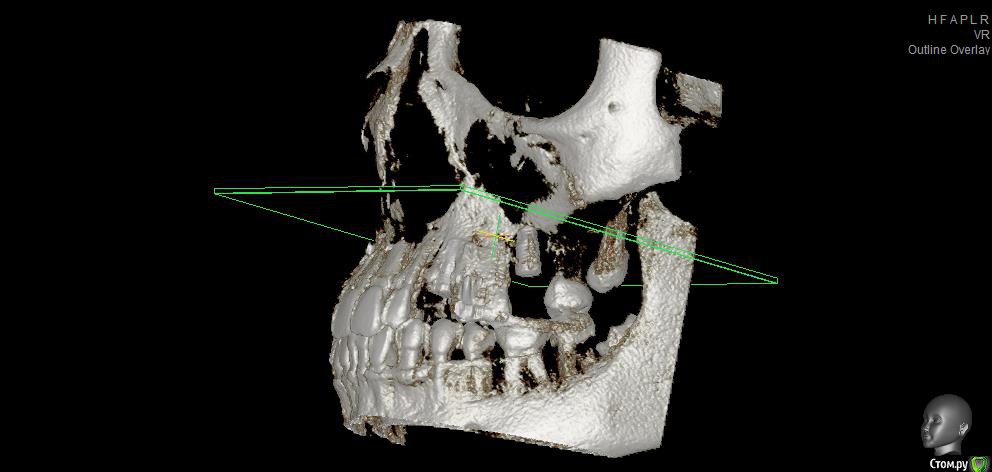

fifa888.dexo Опубликовано 22 июля, 2015 Автор Поделиться Опубликовано 22 июля, 2015 (изменено) Вот панорамный Изменено 22 июля, 2015 пользователем fifa888.dexo Ссылка на комментарий

fifa888.dexo Опубликовано 22 июля, 2015 Автор Поделиться Опубликовано 22 июля, 2015 а это все что я могла придумать с кт Ссылка на комментарий

diesel87 Опубликовано 22 июля, 2015 Поделиться Опубликовано 22 июля, 2015 По ОПТГ, формирователь не докручен, вам уже сказали, имплант в области левого клыка скорее всего не в контакте с четверкой (но надо глянуть КТ), даже если четверка депульпирована, она бы четко отреагировала бы на контакт с имплантом, болью или дискомфортом при накусывании/надавливании. В области синуса воспаление не особо просматривается и материал тоже четко не визуализируется в пазухе. Капать надо сосудосуживающее или гормональное. Выложите еще раз ссылку на КТ, ваши срезы не информативны. Ссылка на комментарий

diesel87 Опубликовано 22 июля, 2015 Поделиться Опубликовано 22 июля, 2015 http://fs2.directupload.net/images/150723/9sv48h7l.jpg http://fs1.directupload.net/images/150723/9nsd29hm.jpg http://fs2.directupload.net/images/150723/q4s456ou.jpg http://fs2.directupload.net/images/150723/9x7h27mc.jpg По КТ:1.возможно имплант в области клыка в апексе (самой верхней части) контактирует с четверкой (не ясно из-за того что имплант фонит), если четверка не реагирует, то пока наблюдать, делать прицельные снимки раз в 3/6/9/12 месяцев.2. Не докрученный формирователь, особо не страшно, но в щель может врасти десна, будет запах, локальное воспаление в области шейки импланта, так что лучше его докрутить или если он упирается в соседние зубы, поменять на узкий и докрутить.3. Имплант что в синусе, по снимку он практически весь в кости, а "воспаление" могло быть там и ранее, есть снимки до операции?? Ссылка на комментарий